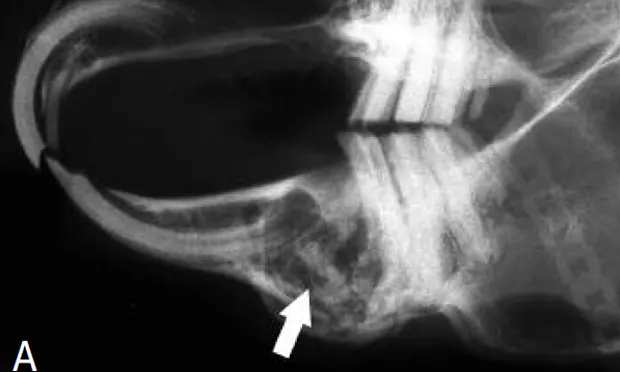

Formation of dental-related abscesses is common in pet rabbits. Most facial abscesses are a sequela to acquired dental disease, particularly dental disease as a result of metabolic bone disease or tooth fracture. Frequently, they develop from periapical infection of mandibular cheek teeth and typically involve both hard and soft tissues. Therefore, common radiographic abnormalities include a fragment of a mandibular cheek tooth associated with mandibular osteomyelitis. The cheek tooth fragment is usually visible in a circular radiolucent lesion that contains purulent material (Figure A).